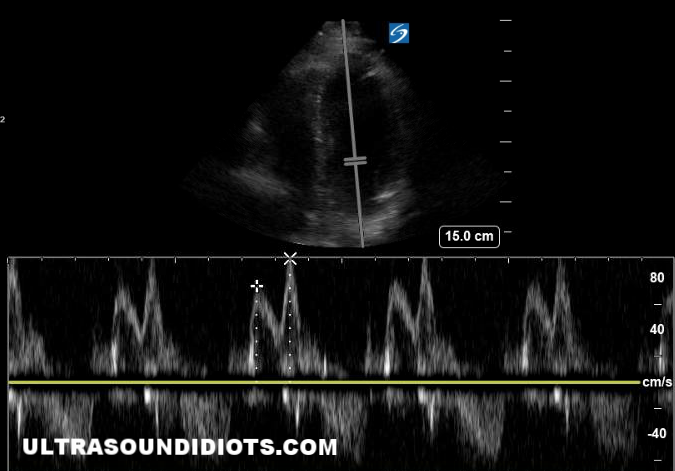

Tricuspid Annular Plane Systolic Excursion (TAPSE) with M-mode

TAPSE <1.6 cm is abnormal